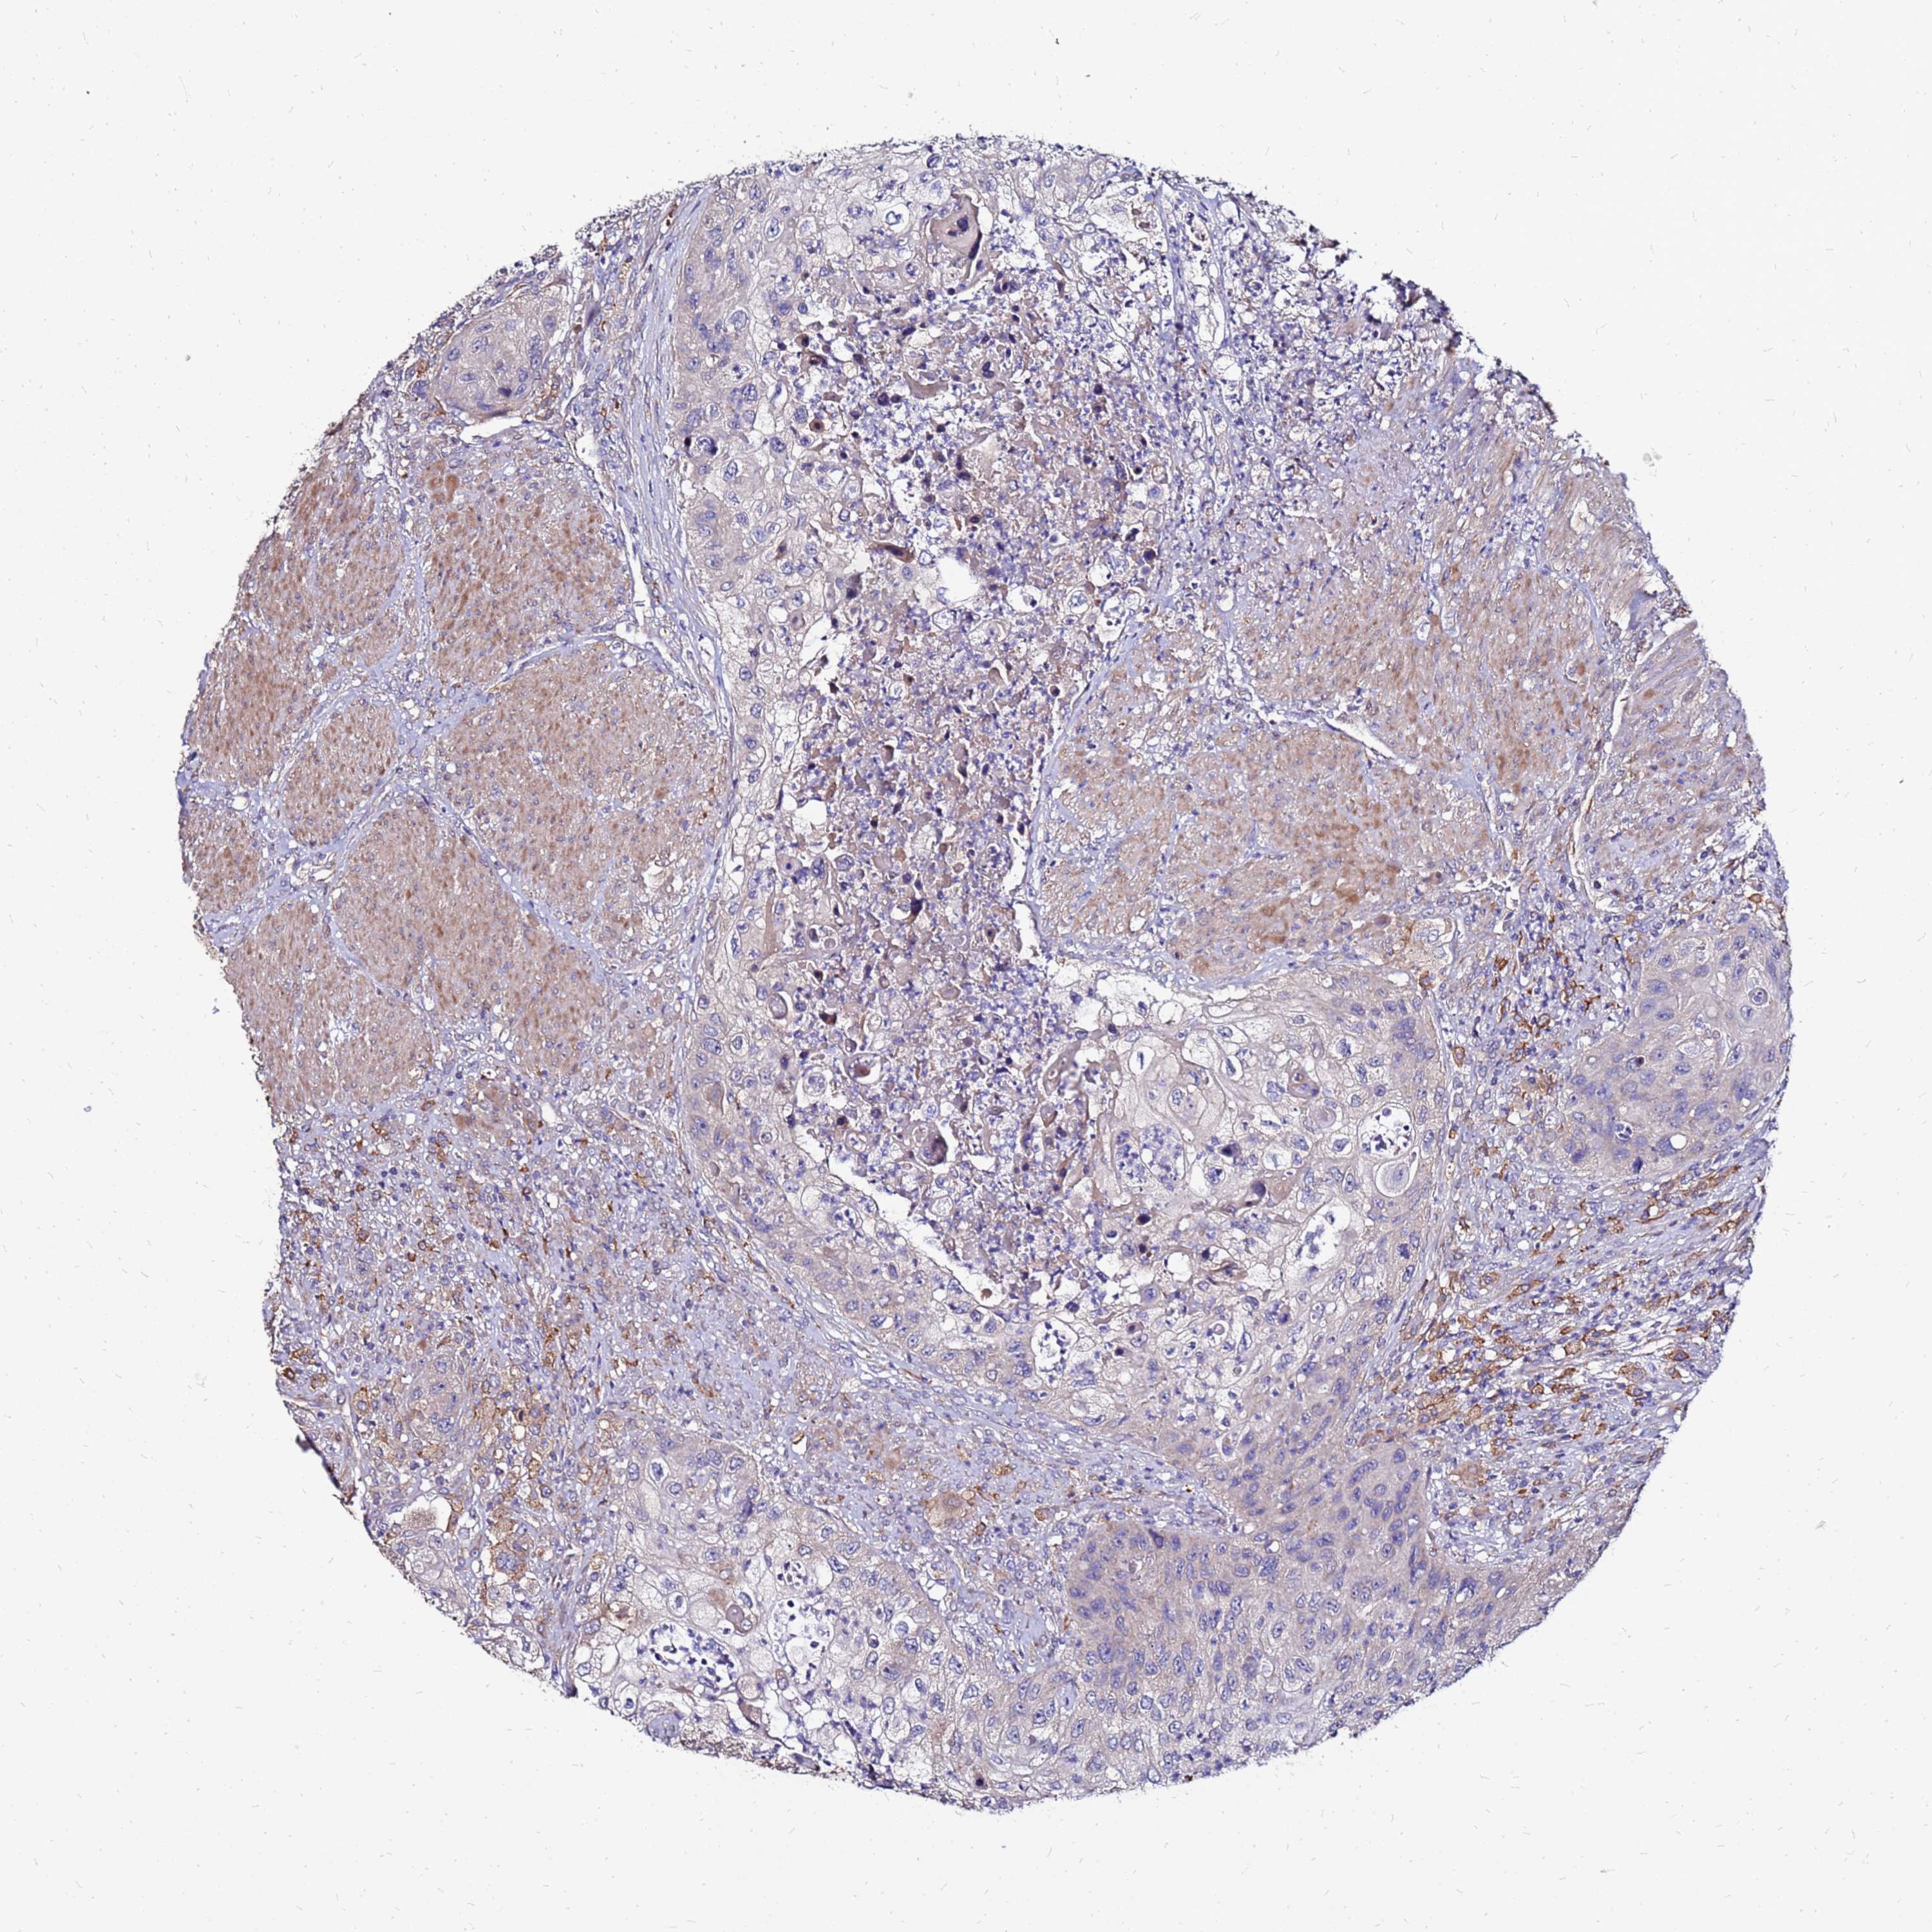

UROTHELIAL CANCER - Protein expressioni

A mouse-over function shows sample information and annotation data. Click on an image to view it in a full screen mode. Samples can be filtered based on level of antibody staining by selecting one or several of the following categories: high, medium, low and not detected. The assay and annotation is described here.

Note that samples used for immunohistochemistry by the Human Protein Atlas do not correspond to samples in the TCGA dataset.

Antibody stainingi

Antibody staining in the annotated cell types in the current human tissue is reported as not detected, low, medium, or high, based on conventional immunohistochemistry profiling in selected tissues. This score is based on the combination of the staining intensity and fraction of stained cells.

Each image is clickable and will lead to virtual microscopy that enables deeper exploration of all samples and also displays staining intensity scores, fraction scores and subcellular localization as well as patient and tissue information for each sample.

Urothelial carcinoma, Low grade

Urothelial carcinoma, High grade